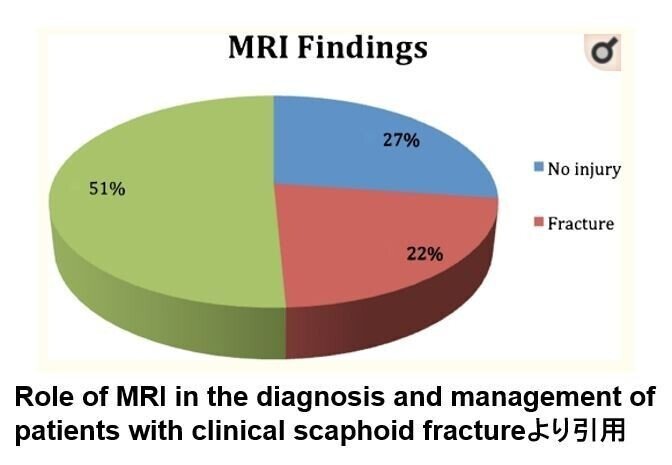

臨床的に舟状骨骨折が疑われ

整形外科により

MRI検査を依頼された患者の統計です

137症例のうち骨折がみられたのは22%だった

それ以外は正常(27%)であり

43.4%が軟部組織損傷だった